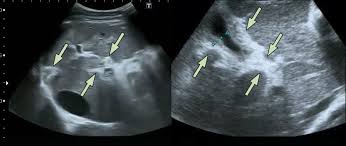

schistosomiasis